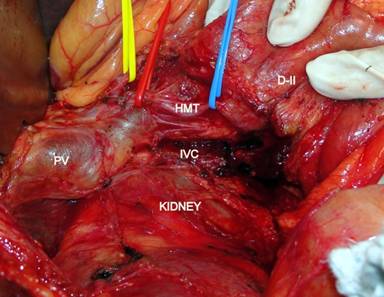

A 45-year-old male presented to the out-patient department with jaundice of 30-day duration. He had no abdominal pain, but gave a history of high colored urine along with pale stools. He also had pruritus along with significant weight loss of 15 kg over the previous two months. His past surgical history was significant for a history of laparoscopic cholecystectomy one year ago; the procedure and the post-operative period was uneventful. On examination, his vital parameters were stable, and apart from icterus, his general examination was unremarkable. Abdomen examination was unremarkable apart from healthy port-site scars. Per-rectal examination revealed pasty pale stools. His complete hemogram and renal function tests were within normal limits. His liver function tests revealed an increased direct fraction of bilirubin (6.08 mg/dL; reference range: 0-1 mg/dL), along with a raised alkaline phosphatase (722 IU/L; reference range: 80-290 IU/L) and gamma glutamyltranspeptidase (243 IU/L; reference range: 7-32 IU/L). An esophagogastroduodenoscopy was done which revealed a prominent ampulla. A side-viewing-scopy of the duodenum was done, which showed an ulcerated growth at the ampulla, a biopsy of which was inconclusive, with atypical cells. Imaging of the abdomen showed intrahepatic and extrahepatic biliary radical dilatation with obstruction at the level of the ampulla. The main pancreatic duct was also dilated up to the ampulla (Figure 1). CA 19-9 was done which was elevated at 74.28 ng/mL (reference range: 0-10 ng/mL). The patient was optimized and was taken up for a planned pancreaticoduodenectomy for the ampullary growth. Intraoperatively, on evaluation of the superior border of the pancreas, common hepatic artery was found to be absent. Further kocherization and careful dissection of the hepatoduodenal ligament revealed a replaced common hepatic artery arising from the superior mesenteric artery which was coursing through the uncinate process, posterior to the duodenum and portal vein. The artery crossed the portal vein laterally to lie anterior to the common bile duct at the superior border of the pancreas, where it divided into the left and right hepatic arteries (Figure 2). The gastroduodenal artery was absent; the right gastric artery arose from the left hepatic artery. Following an extended kocherization and hilar dissection, complete course of the artery was delineated. Pancreas was transected at the neck anterior to the portal vein and the uncinate process was successfully dissected free from the common hepatic artery (Figure 3). A pylorus preserving pancreaticoduodenectomy was completed. Patient developed grade I delayed gastric emptying (International Study Group for Pancreatic Surgery Criteria), which improved with conservative management. Rest of his post operative period was uneventful, and he was discharged on the 14th postoperative period. Histopathology revealed an ampullary adenocarcinoma, with all margins being free from tumor.

Figure 2. Post kocherization course of the hepatomesenteric trunk. D-II: second part of duodenum; HMT: hepatomesenteric trunk; IVC: inferior vena cava; PV: portal vein |